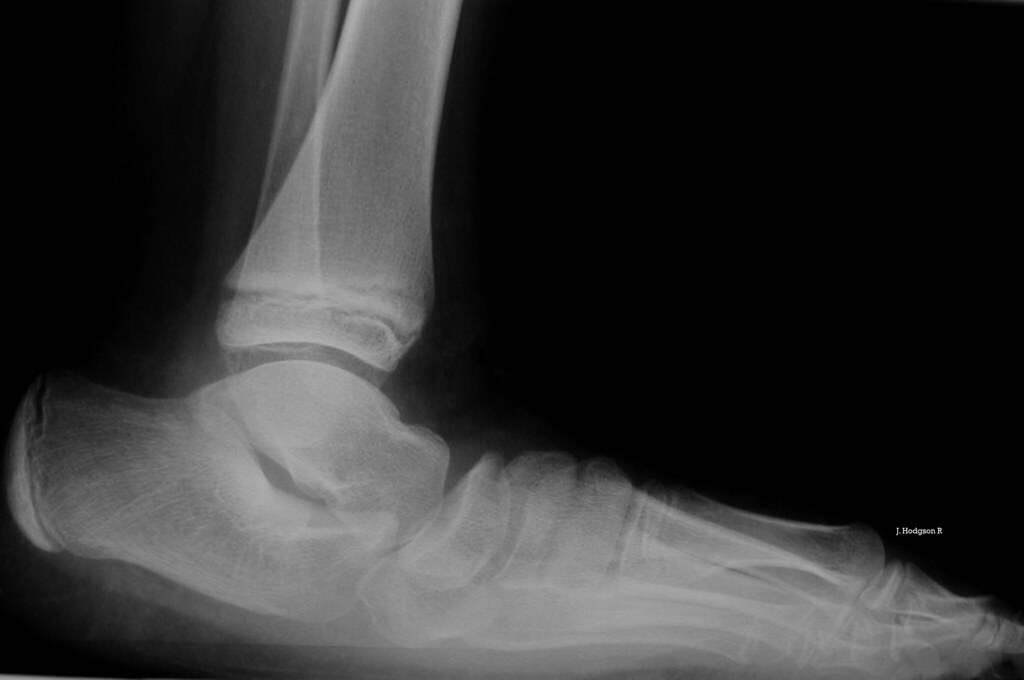

Valgus Vs Varus Of Ankle Pie Valgo In English Check 'pie plano valgo' translations into english. I'm worth valgus i am worth am i worth. Look through examples of pie plano valgo translation in sentences, listen to pronunciation. Por otro lado, no debe descuidarse la supervisión simultánea de todo el eje de la pierna, pues el genu valgo. Finalmente tengo la oportunidad de. Translate pie valgo from spanish to. Pie Valgo In English.